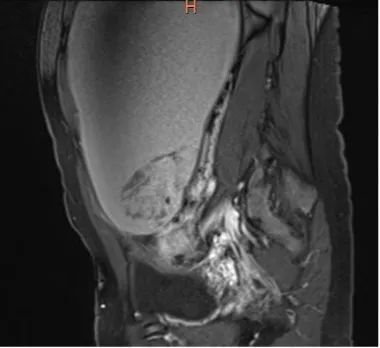

住院后进一步的检查结果令人瞠目。盆腔MRI发现了娇小瘦弱的她肚子里竟藏着一个30多公分的大包块,霸占了几乎整个盆腹腔,盆腔血管里也有血栓形成。

至此,拨开云雾见天日,一切谜团都解开了:就是小罗肚子里的小怪物的压迫,导致左下肢及盆腔静脉血栓形成,脱落的栓子游走到肺动脉,造成了危及生命的急性肺动脉栓塞。

小罗隆起的肚子就好像怀孕7-8个月,这个性质不明的巨大肿块,还在慢慢长大,如果压迫不解除,不但会形成新的血栓,而且会压迫肠管,小罗那几天被腹部的胀痛折磨,胃口也已变得很差,并出现了贫血症状。